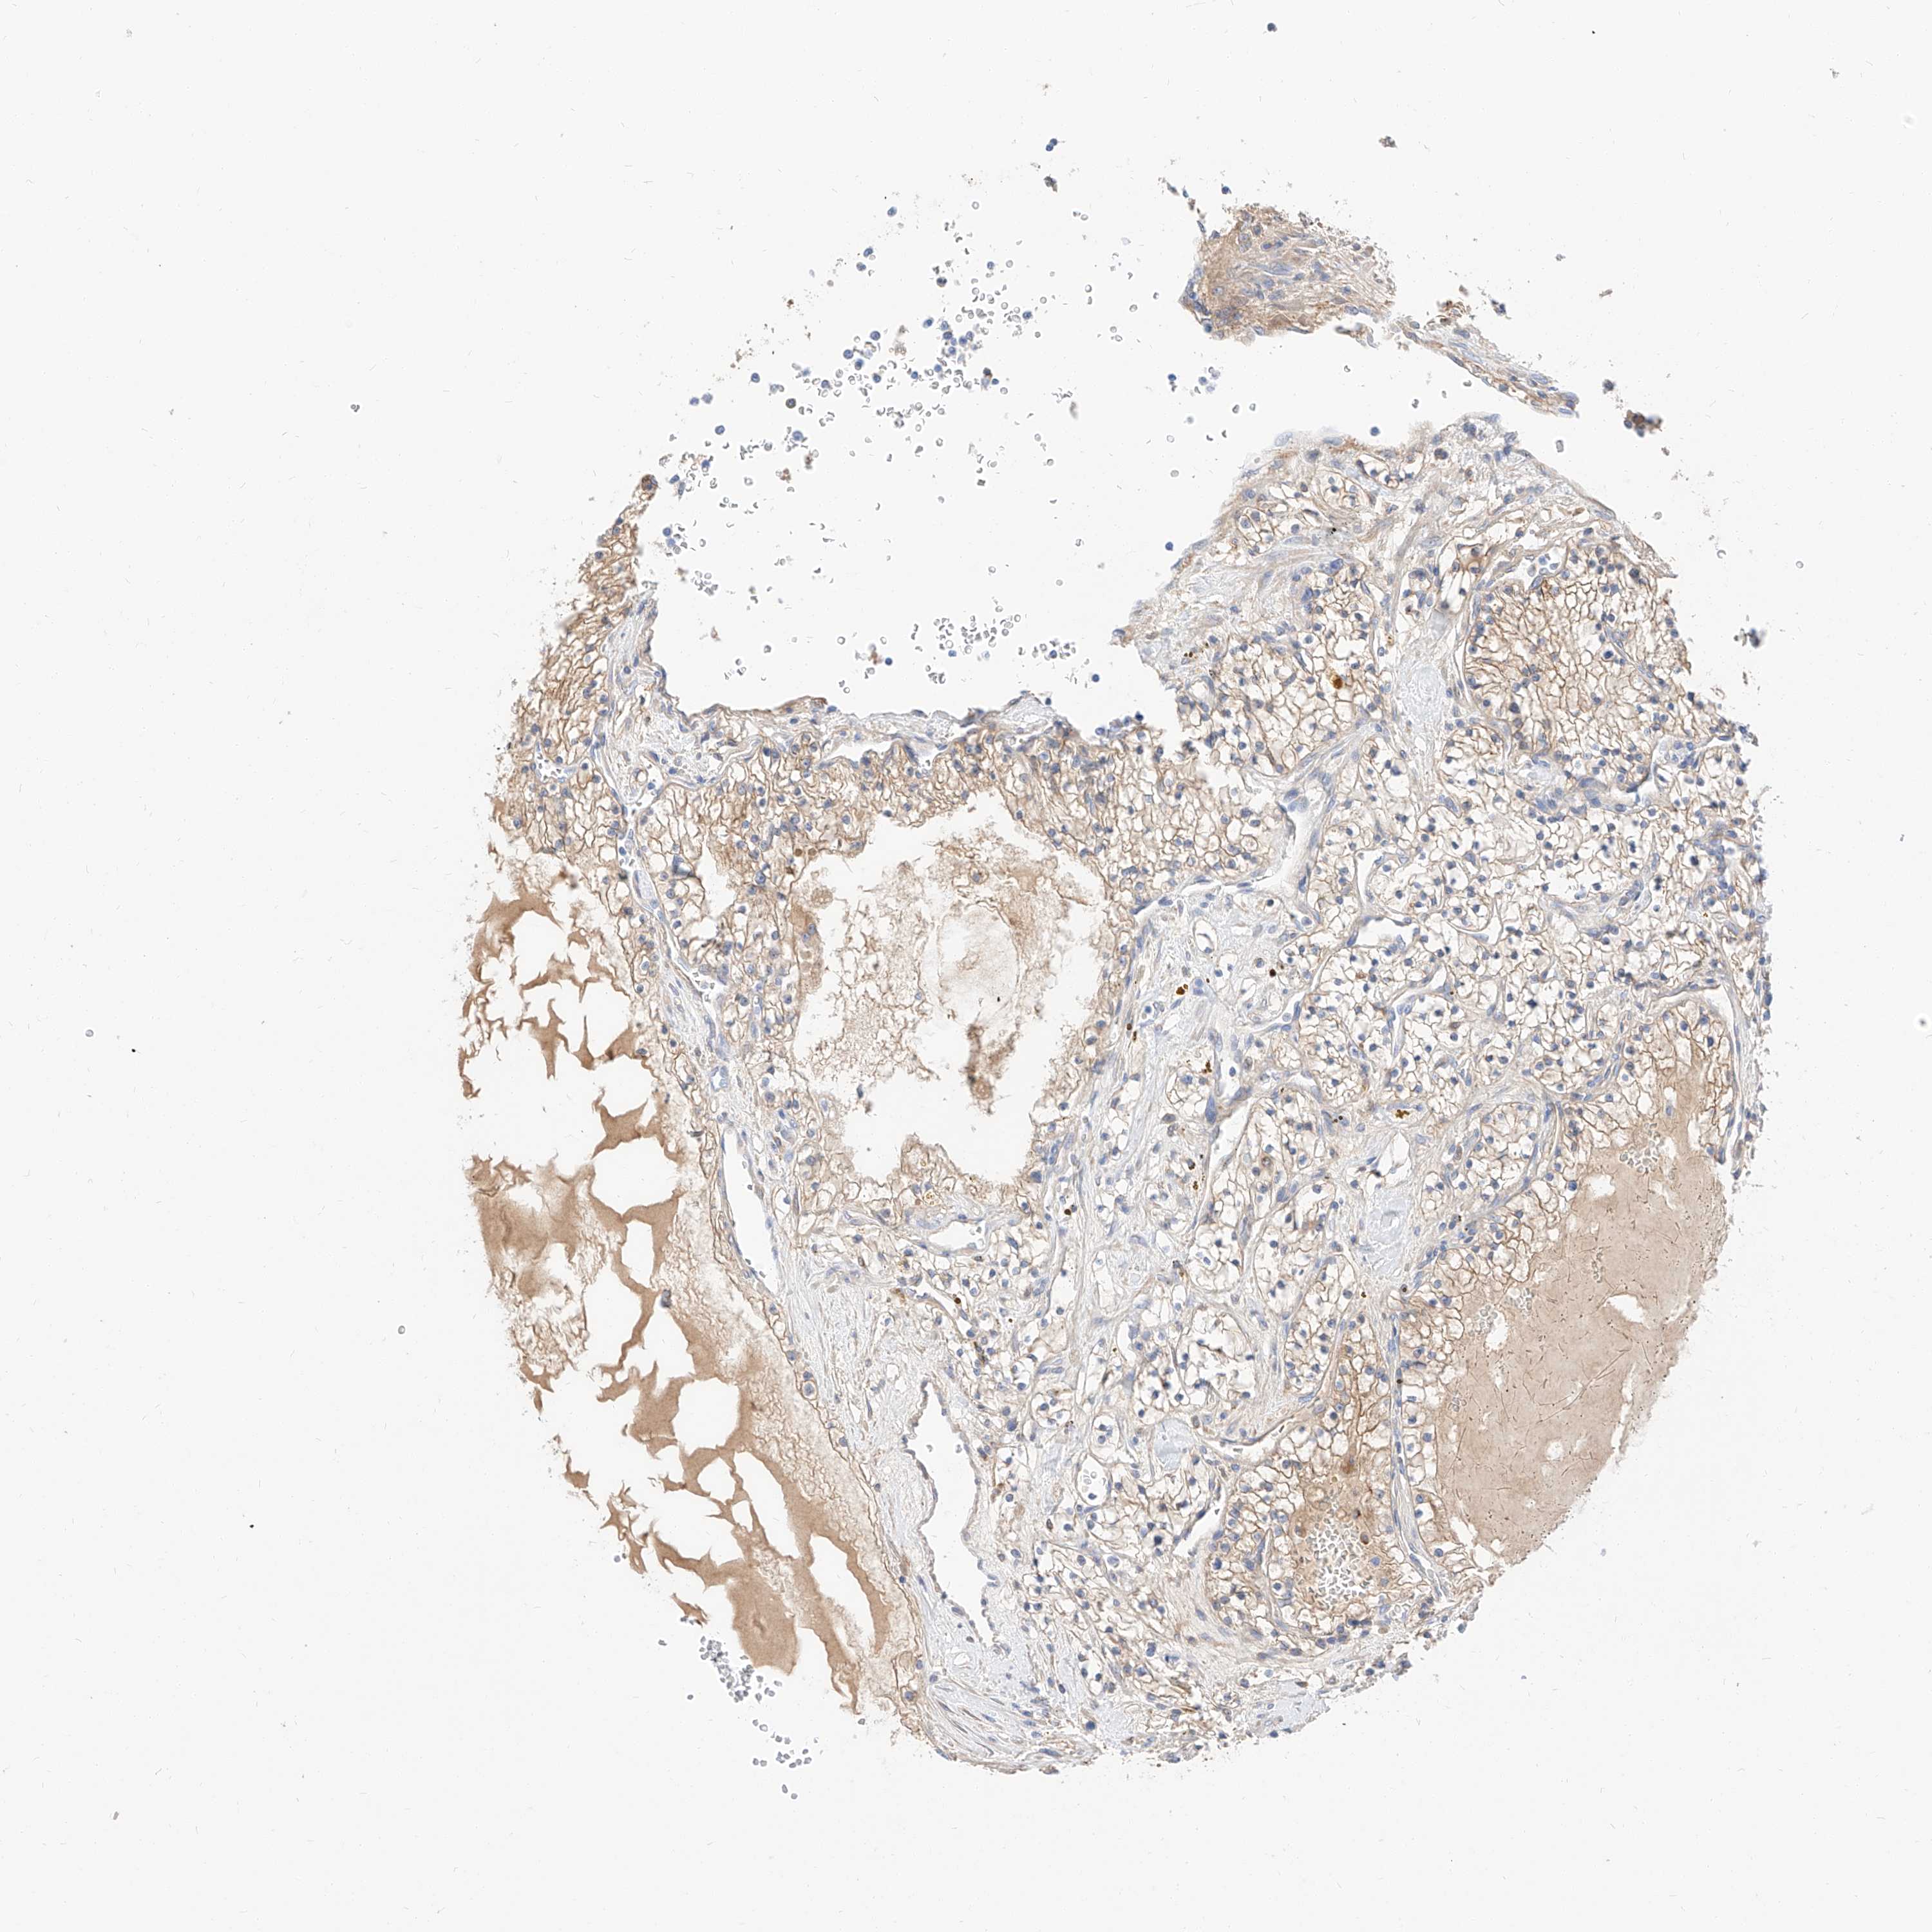

KIDNEY RENAL CLEAR CELL CARCINOMA (VALIDATION) - Interactive survival scatter ploti

The Survival Scatter plot shows the clinical status (i.e. dead or alive) for all individuals in the patient cohort, based on the same data that underlies the corresponding Kaplan-Meier plots. Patients that are alive at last time for follow-up are shown in blue and patients who have died during the study are shown in red.

The x-axis shows the expression levels (FPKM) of the investigated gene in the tumor tissue at the time of diagnosis. The y-axis shows the follow-up time after diagnosis (years). Both axes are complimented with kernel density curves demonstrating the data density over the axes. The top density plot shows the expression levels (FPKM) distribution among dead (red) and alive patients (blue). The right density plot shows the data density of the survived years of dead patients with high and low expression levels respectively, stratified using the cutoff indicated by the vertical dashed line through the Survival Scatter plot. This cutoff is automatically defined based on the FPKM cutoff that minimizes the p-score. The cutoff can be changed by dragging the vertical line or by entering a cutoff value in the square labeled "Current cut-off".

Under the Survival Scatter plot the p-score landscape (black curve; left axis) is shown together with dead median separation (red curve; right axis). Dead median separation is the difference in median mRNA expression between patients who have died with high and low expression, respectively. It is calculated as follows: median FPKM expression of dead patients with high expression - median FPKM expression of dead patients with low expression. This is intended to aid the user in visually exploring custom cutoffs and the associated p-scores and dead median separation.

Individual patient data is displayed and can be filtered by clicking on one or more of the category buttons on the top of the page. Categories describing expression level and patient information include: high, low, alive, dead, female, male and tumor stages. The scale of the x-axis can be toggled between linear and log-scale by clicking on the "x log" button. Mouse-over function shows TCGA ID, patient information and mRNA expression (FPKM) for each patient.

& Survival analysisi

Kaplan-Meier plots summarize results from analysis of correlation between mRNA expression level and patient survival. Patients were divided based on level of expression into one of the two groups "low" (under cut off) or "high" (over cut off). X-axis shows time for survival (years) and y-axis shows the probability of survival, where 1.0 corresponds to 100 percent.

MAP7 is validated prognostic, high expression is favorable in Kidney Renal Clear Cell Carcinoma (validation)

Best expression cut offi

Based on the FPKM value of each gene, patients were classified into two groups and association between prognosis (survival) and gene expression (FPKM) was examined. The best expression cut-off refers the FPKM value that yields maximal difference with regard to survival between the two groups at the lowest log-rank P-value. Best expression cut-off was selected based on survival analysis .

When clicking on this number, the vertical dashed line indicating cut-off, the interactive survival plot, and the Kaplan-Meier curve will be adjusted to show results based on the best expression cut-off.

: 10.69

TCGA RNA samplesi

RNA-seq data is reported as average FPKM (number Fragments Per Kilobase of exon per Million reads), generated by the The Cancer Genome Atlas (TCGA) .

Normal distribution across the dataset is visualized with box plots, shown as median and 25th and 75th percentiles. Points are displayed as outliers if they are above or below 1.5 times the interquartile range. FPKM values of the individual samples are presented next to the box plot.

Average pTPM 29.0

Number of samples 100